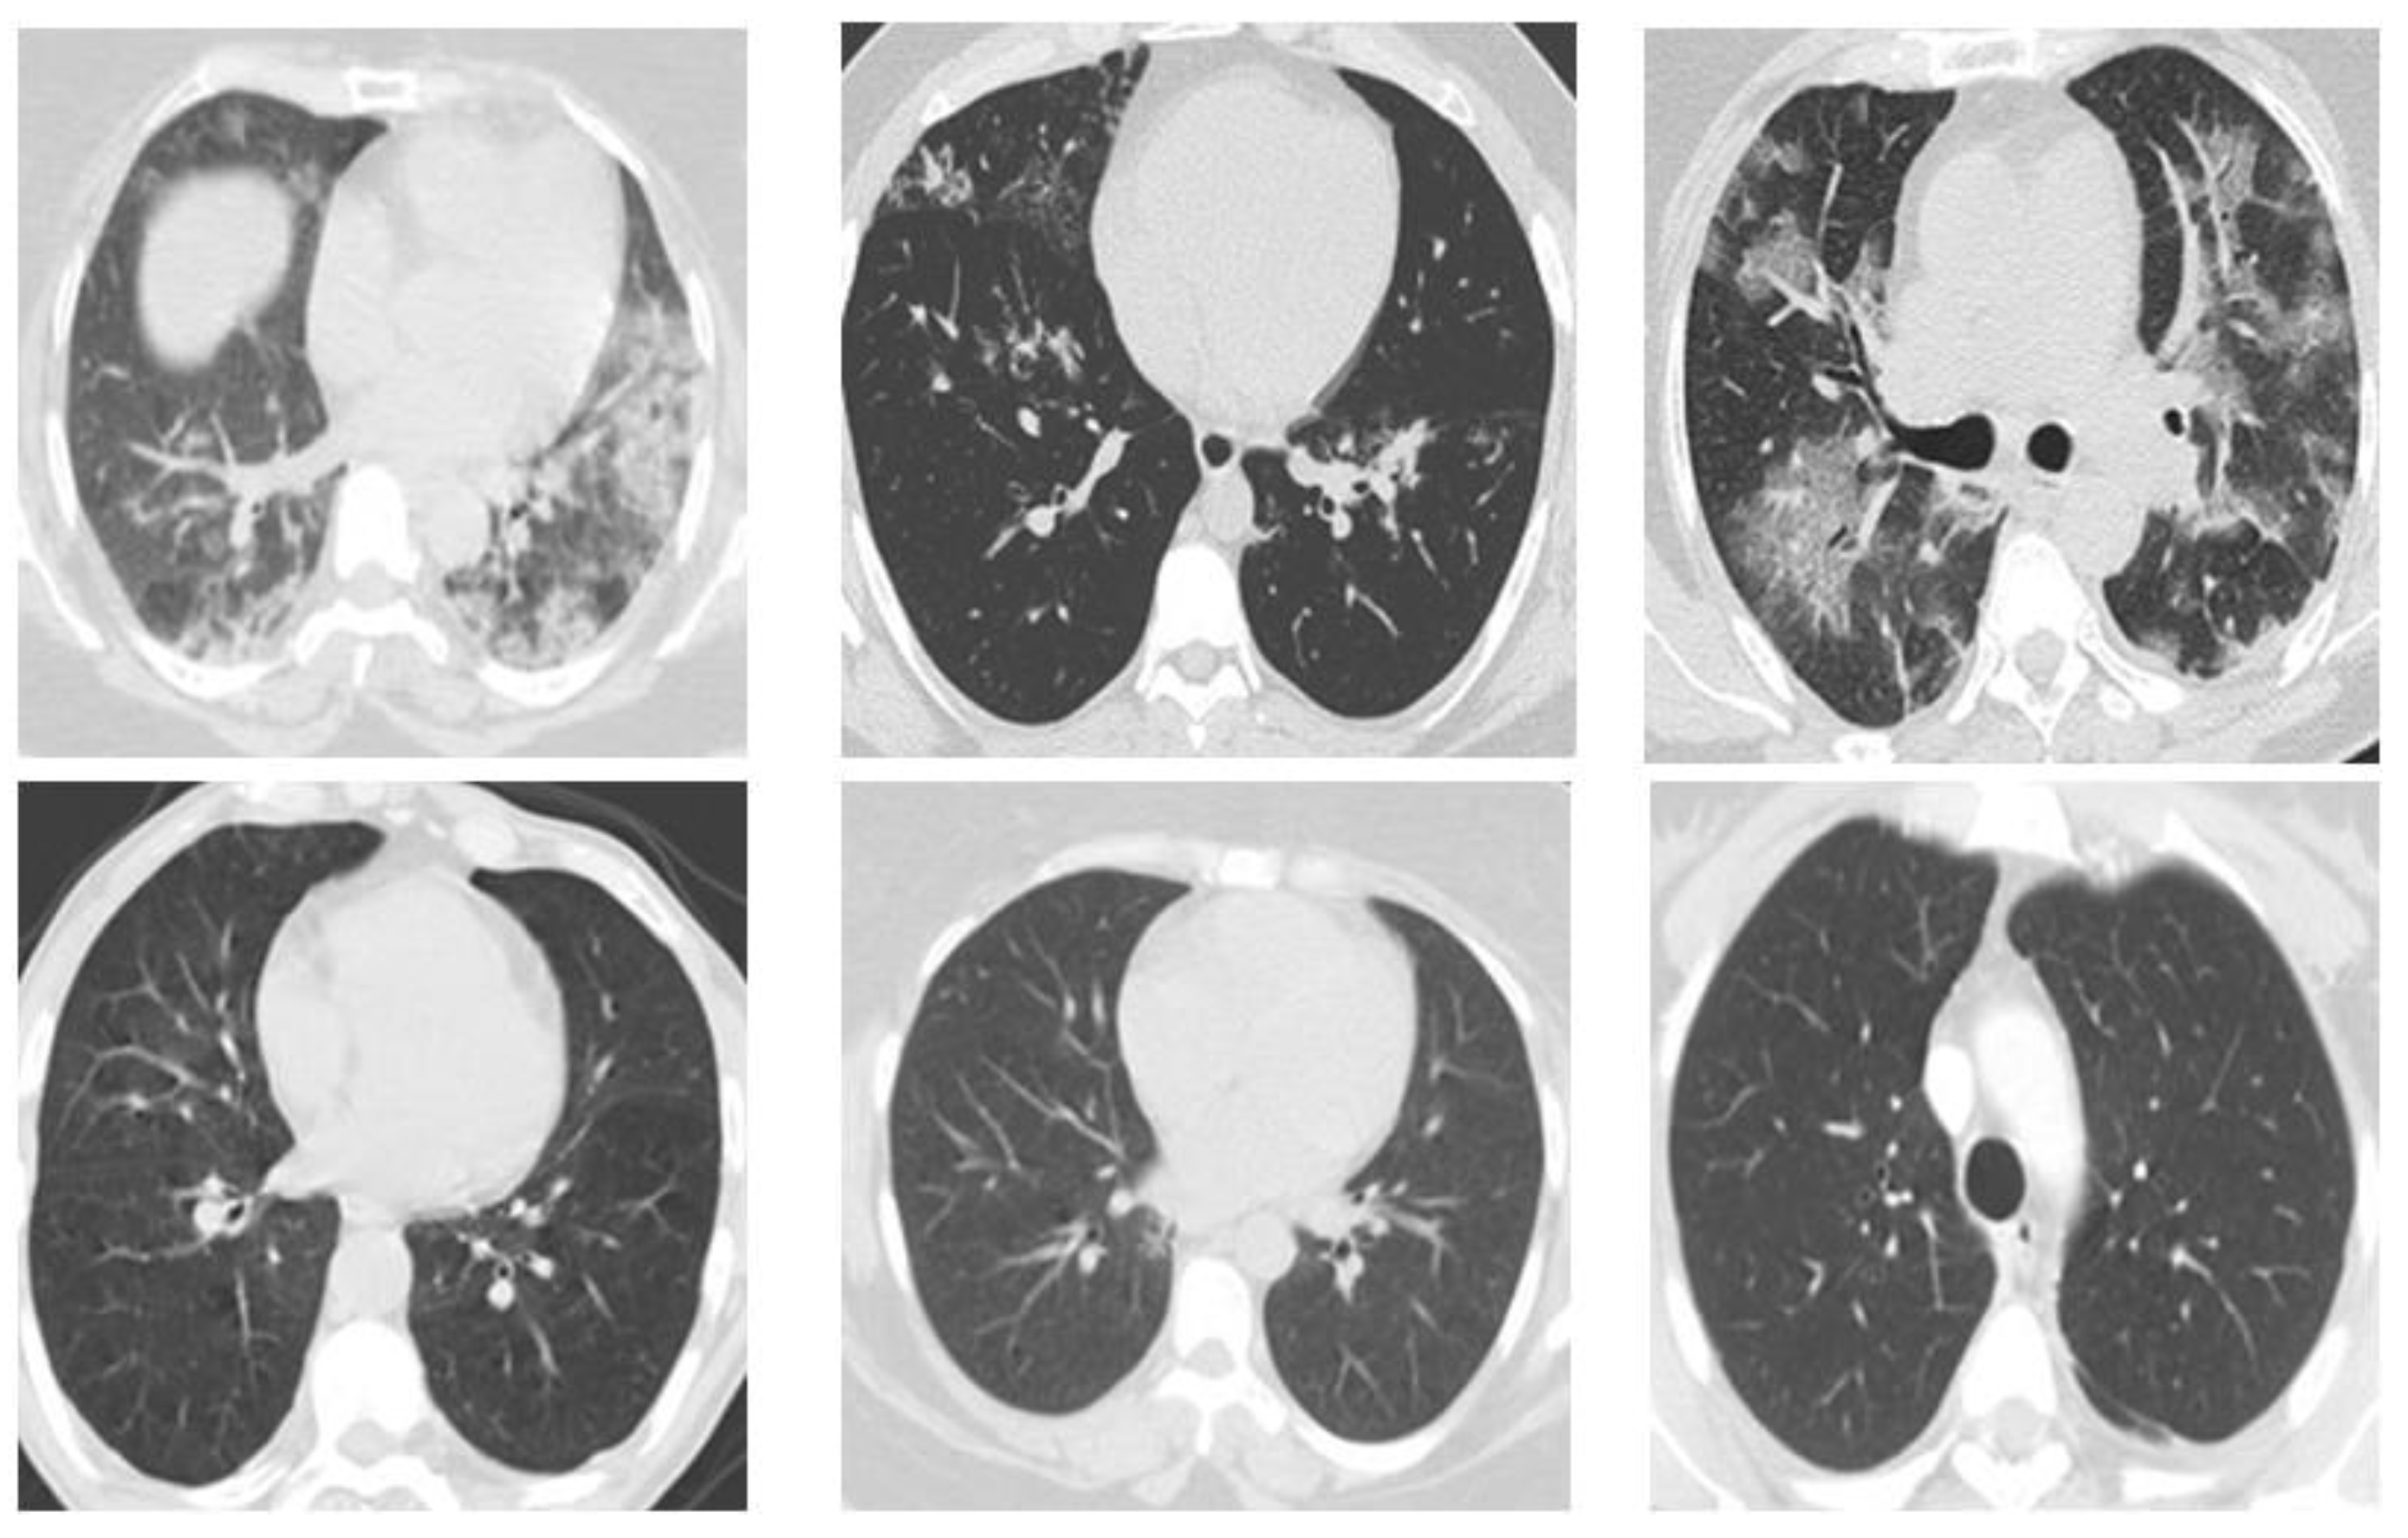

The suggested dataset (SARS-COV-2) contains 2481 CT images shared among 1252 patients infected with COVID-19 and 1229 CT scans for non-Covid patients. Data were gathered from hospitals in Sao Paulo, Brazil. In this case, the data consist of 60 patients infected with Coronavirus 28 of them were female and 32 were male [37]. The size of the images in this database was different; the size of all the images equalized before the pre-processing stage. (Figure 2)

Figure 2. Database sample images.